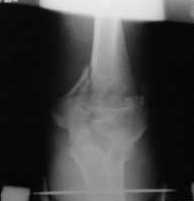

Подскажите пожалуйста, как можно в дальнейшем этому больному помочь. В марте первая операция, пришлось оперировать на 16 сутки в виду инфицированных садин и анемии. Заживление первичным натяжением,раняя разработка после операции, а через 2 нед болевой синдром,и постепенно движения в локтевом суставе ограничились до полного анкилоза. Повторно через 4 месяца вторая операция" артролиз,удаление оссификатов, удаление фиксаторов, реостеосинтез этой же реконструкционной пластиной и винтом" интраоперационно после удаления оссификатов и фиксаторов обнаружил, что перелом не сросшиеся, поэтому пришлось синтезировать заново. Зажило рана первично, объем движений в локтевом суставе сгибание 70, разгибание160, ротационные движения востановились полностью,вроде бы успокоились. Опять постепенно в течении 8 нед после повторной операции постепенно движения ограничились до 80 - 110, на снимке оссификат. Снимки во вложении, буду рад Вашим советам. Спасибо!